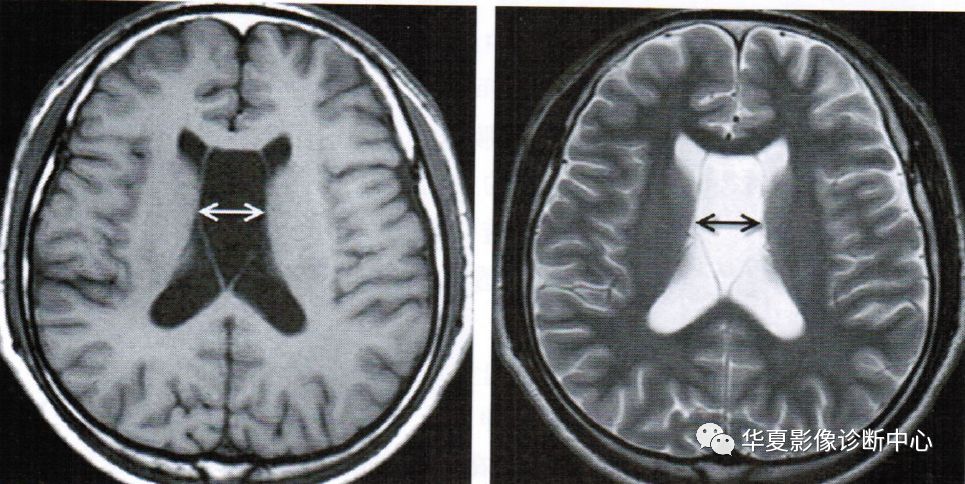

透明隔间腔出现在第三脑室上部层面,位于侧脑室额角之间,呈条带状、三角形、类梯形脑脊液密度,边界清楚,两侧壁多平行向后直抵侧脑室室间孔,两侧壁之间宽度最少要>1mm且<10mm

上图为透明隔囊肿

透明隔囊肿表现为透明隔两侧壁弯曲甚至膨隆,失去正常平行状态,且侧壁间距>10mm